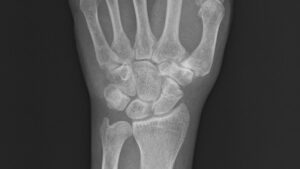

市内の病院を受診し、レントゲン撮影を行った結果、左手の舟状骨に骨折線が確認された。

舟状骨は、手首の親指側に位置する小さな手根骨で、転倒時に手をついた際の衝撃が集中しやすい部位である。

さらに、血流が乏しい骨であるため、骨癒合遅延や偽関節になりやすいことが医療者の間ではよく知られている。

下図は手術前の左手レントゲン写真で、中央の船状骨が砕けている様子が見える。

以下の5枚は再発後、手術直前に撮影されたレントゲン写真である。正面像では舟状骨遠位部に骨折線が見え、斜位像および側面像では骨片のずれが明確に確認できる。

/レントゲン写真を角度を変えて5枚撮影